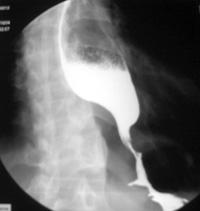

食管贲门失弛缓症